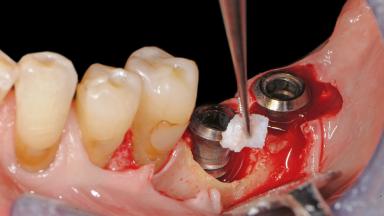

Surgical Treatment of Peri-Implantitis in the Posterior Mandible Associated with Hard- and Soft-Tissue Reconstruction

Paolo Casentini demonstrates that peri-implantitis can be successfully treated even at an advanced stage. He discusses a case in which the existing implants and prostheses were both retained while regenerating the defect and creating a band of keratinized tissue. A 69-year-old female patient was referred by her general dentist for evaluation of a recurrent infection at previously placed and restored implants in the posterior left mandible. The patient’s chief complaint was recurrent swelling and pain in the molar region of the left posterior mandible with discomfort during brushing in the same area. The patient reported receiving two implants (36 and 37) nine years earlier.